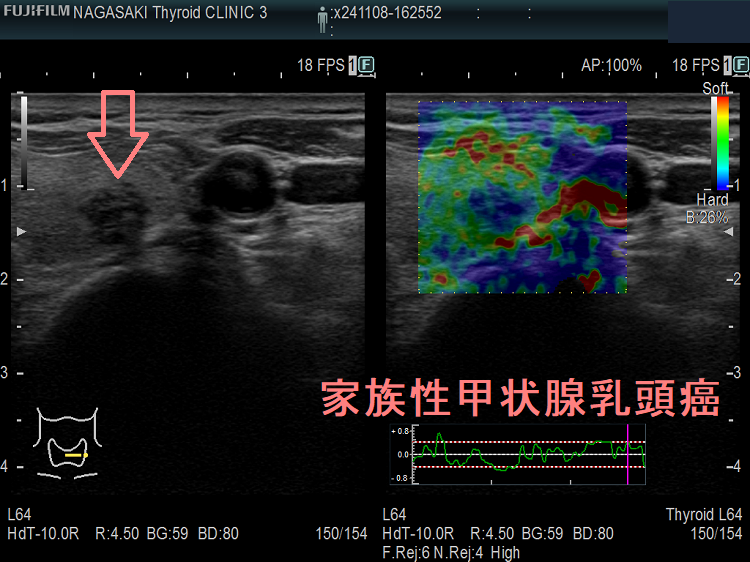

甲状腺癌の85%を占める甲状腺乳頭癌の5-8%は遺伝性であり、多くは常染色体優性遺伝と考えられています。第一度近親者に3名以上見つかれば家族性甲状腺乳頭癌とほぼ確定されます。血縁者内でBRAFという遺伝子の同じ個所に変異が証明できます。

近親者が甲状腺乳頭癌をされている方は、甲状腺超音波(エコー)検査が必要です。

また、御自分が甲状腺乳頭癌なら、血縁者の甲状腺超音波(エコー)検査が必要です。

家族性非髄様癌性甲状腺癌(FNMTC)は、おもに甲状腺乳頭癌で前述のことです(甲状腺濾胞癌もありますが)。遺伝形式は、不完全浸透の常染色体優性遺伝(要するに50%の確率で遺伝する)です。

患者本人と、第一度近親者(両親、兄弟姉妹、子供)に2名以上の非髄様性甲状腺がん(甲状腺乳頭癌・甲状腺濾胞癌)患者が存在し、かつ、明らかな症候群(表1の遺伝性甲状腺腫瘍)を伴わないものです。3名以上で95%以上、2名以上で50%遺伝性があります。